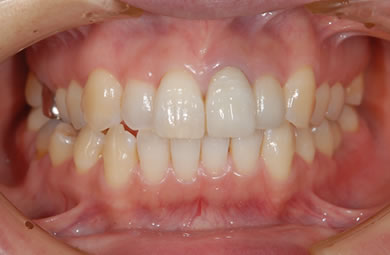

インプラント治療+セラミック治療

| 主訴 | 前歯を白くしたい。 | ||||||||||||||||||||||||||||||||

| 治療方針 | 前歯部の審美的回復をセラミック治療で行う。臼歯部の審美的・機能的回復をインプラント治療で行う。 | ||||||||||||||||||||||||||||||||

| 治療内容 | インプラント1本、メタルボンドセラミック1本、オールセラミック2本(オールセラミック用の土台2本) | ||||||||||||||||||||||||||||||||

| 総治療費 | 608,667円 | ||||||||||||||||||||||||||||||||

| 治療期間 | 4ヶ月 |